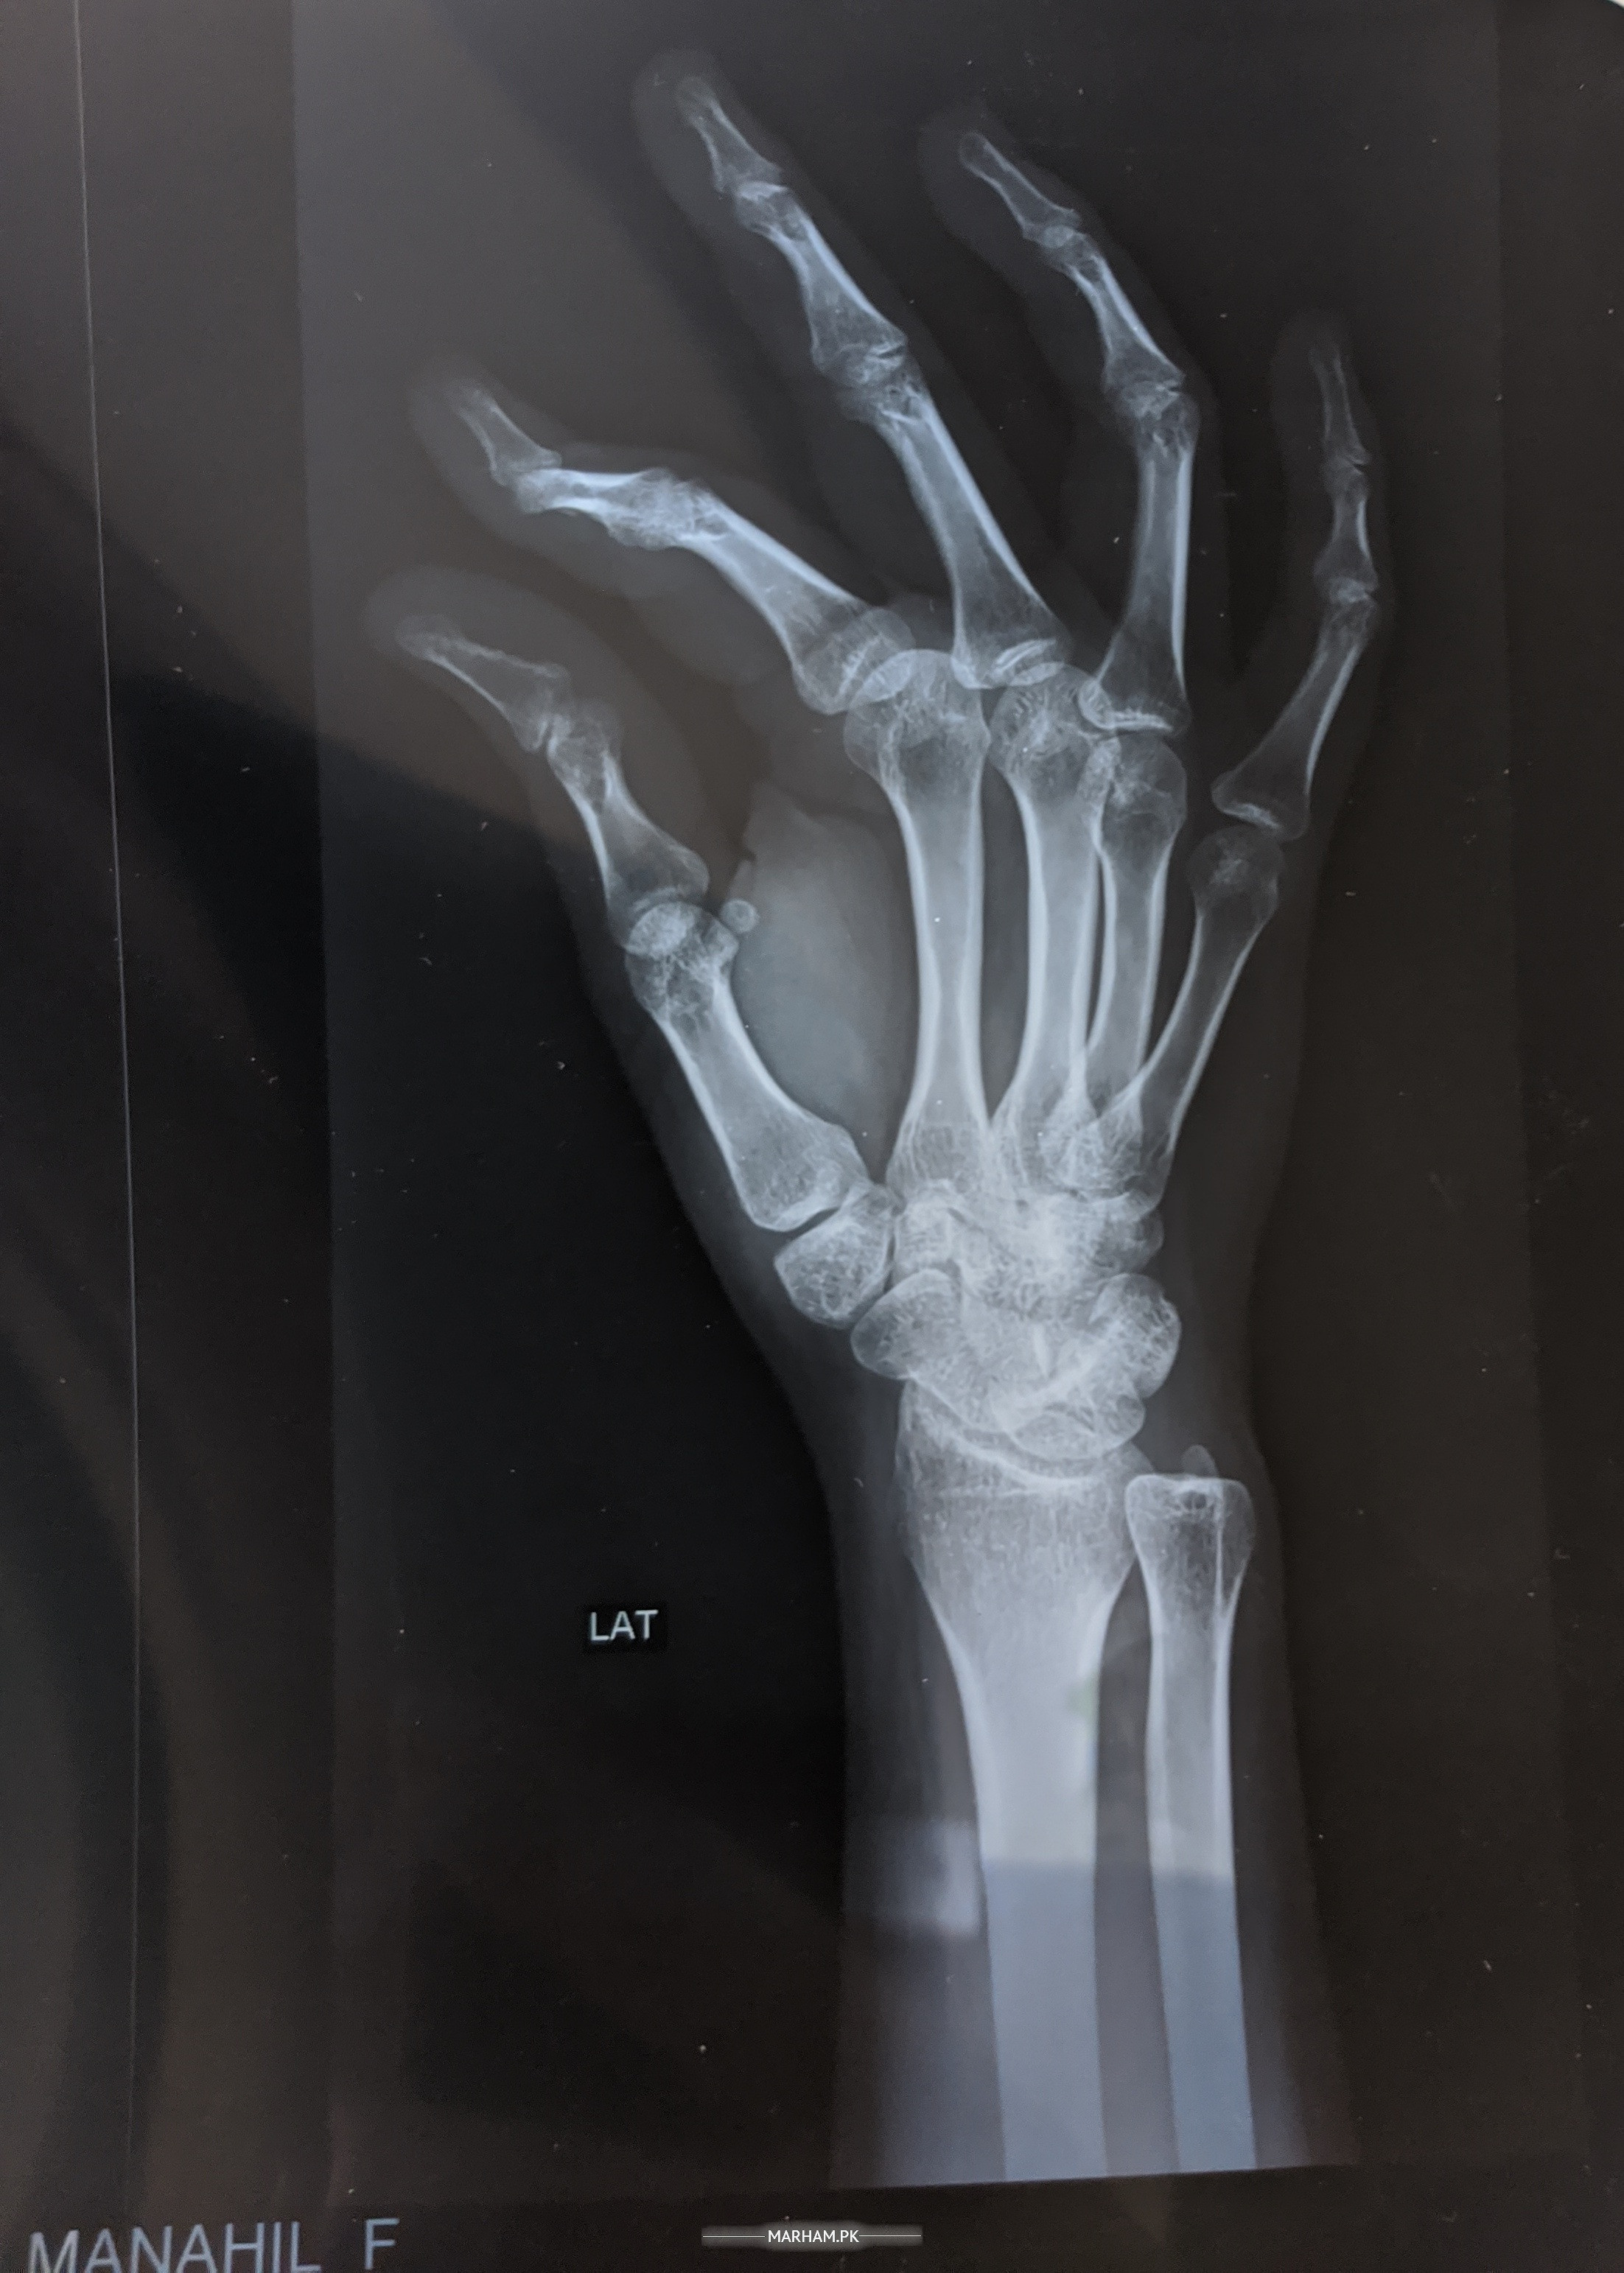

I'm 21 years old but I'm weak. I get unconscious some times..I have severe pain in my right wrist .. I can't bend it and even accidently bended it hurts a lot. I've got my x rays done from various hospitals... each of them said its weakness. please suggest something.

plz share ur x-ray with us do vit D3

Please check I posted my x-rays

X-ray

aap bone density karain aur jo mein nay test deay wo bhi